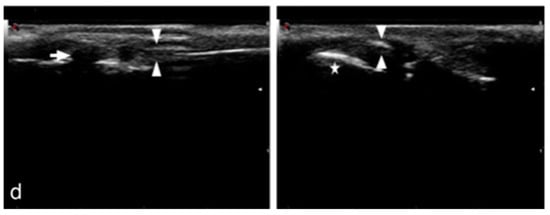

2.2.3. Ultrasonographic Examination

2.3.3. Ultrasonographic Examination